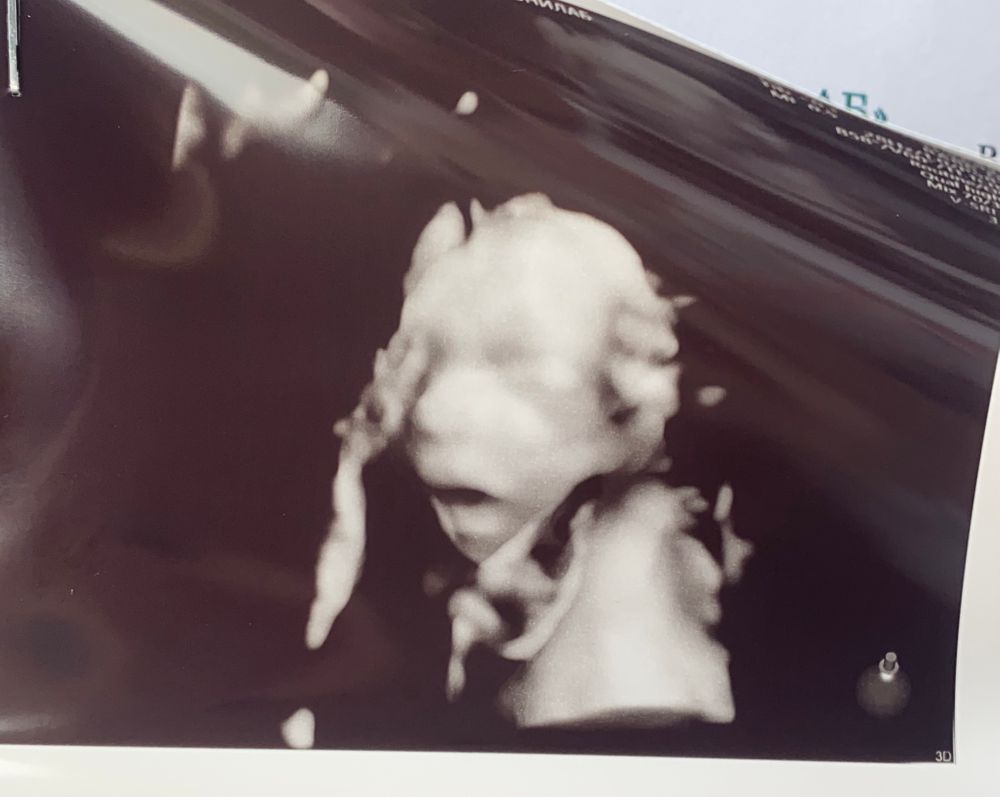

УЗИ, КТГ, доплерПрошла второй скрининг на сроке 19+5, муж сидел с замиранием сердца и смотрел на экран, я только и улыбалась! Блин, первый раз такое увидеть, это что-то с чем-то, словами просто не описать этот момент.

по узи все хорошо, сроку берем соответствуем, пдр 5-8 декабря) ждём декабренка своего 💕💕💕💕

Жучок уж очень не хотел фотографироваться, мой таз был интереснее для него) единственное не чувствую шевеления, от слова совсем, врач сказал все будет на этой неделе)